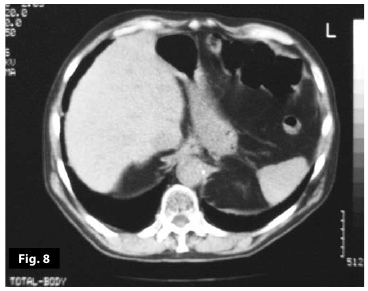

Figure8